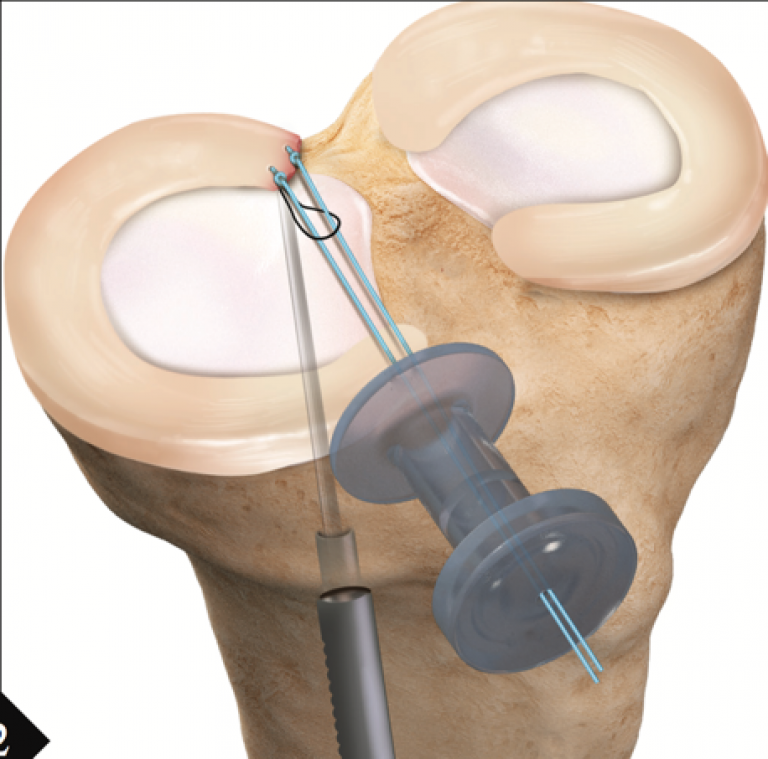

It has been long known that the meniscus is a key structure in the knee providing load share for the joint surface. In the knee